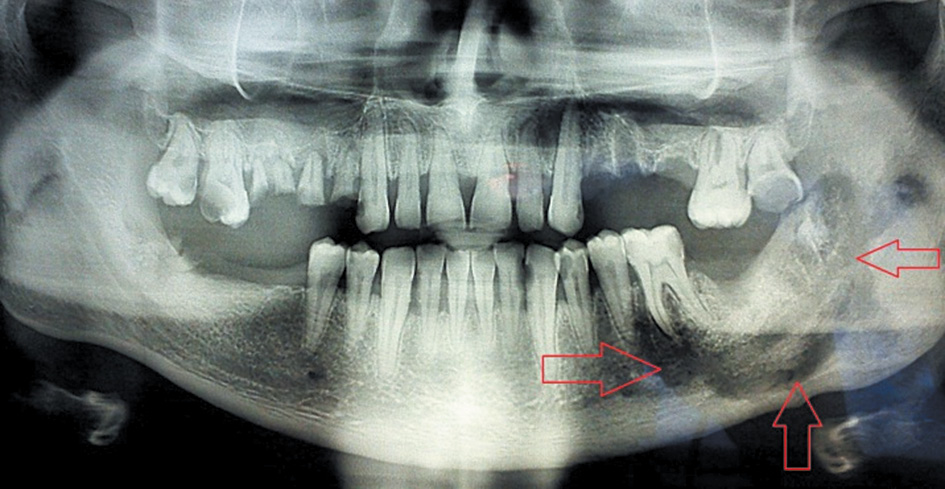

Group 2 (27 patients, including 16 males and 11 females) was characterized by the presence of the signs of sequestration, as a clear demarcation line was found according to OPTG and CBCT of the jaws (Fig. 1).

Fig. 1. Osteonecrosis of the mandible on the left side. The appearance of the demarcation line / Рис. 1. Остеонекроз нижней челюсти слева. Появление демаркационной линии

In addition, the sizes of sequesters varied from an isolated area of the alveolar process within 2–3 teeth to damage in half of the jaw and more. A characteristic was identified in 10 patients with a full-width mandibular lesion. A pronounced thickening and ossification of the surrounding periosteum were found in the form of stratification with the formation of a “bone sheath” surrounding the formed sequestrum, with a width of 5 mm to 1.2 cm (Fig. 2).